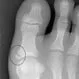

Broken ToeBroken toes are a common fracture for people of all ages. The little toe (pinky) is the most common toe fractured. Most broken toes can be treated with ice, elevation, rest, and buddy taping the broken toe. Learn about complications and recovery time.

BunionsBunions are an enlargement of the inner portion of the joint at the base of the big toe. The symptoms of bunions include inflammation, redness, tenderness, and pain of the first metatarsophalangeal joint. The little toe may also develop a bunion (tailor's bunion).

Picture of HammertoesA hammertoe is a toe that is bent because of a weakened muscle. See a picture of Hammertoes and learn more about the health topic.